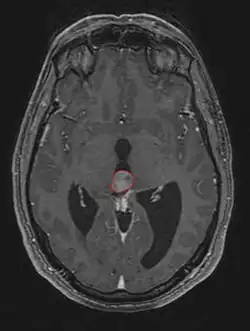

Frequently, paralysis of upward gaze along with several ocular findings such as convergence retraction nystagmus and eyelid retraction also known as Collier's sign and Light Near Dissociation (pupil accommodates but doesn't react to light) are known collectively as Parinaud's syndrome[1] or Dorsal Mid-brain syndrome, are the only physical symptoms seen. This is caused by the compression of the vertical gaze center in the midbrain tectum at the level of the superior colliculus and cranial nerve III. Work-up usually includes Neuro-imaging as seen on the right.